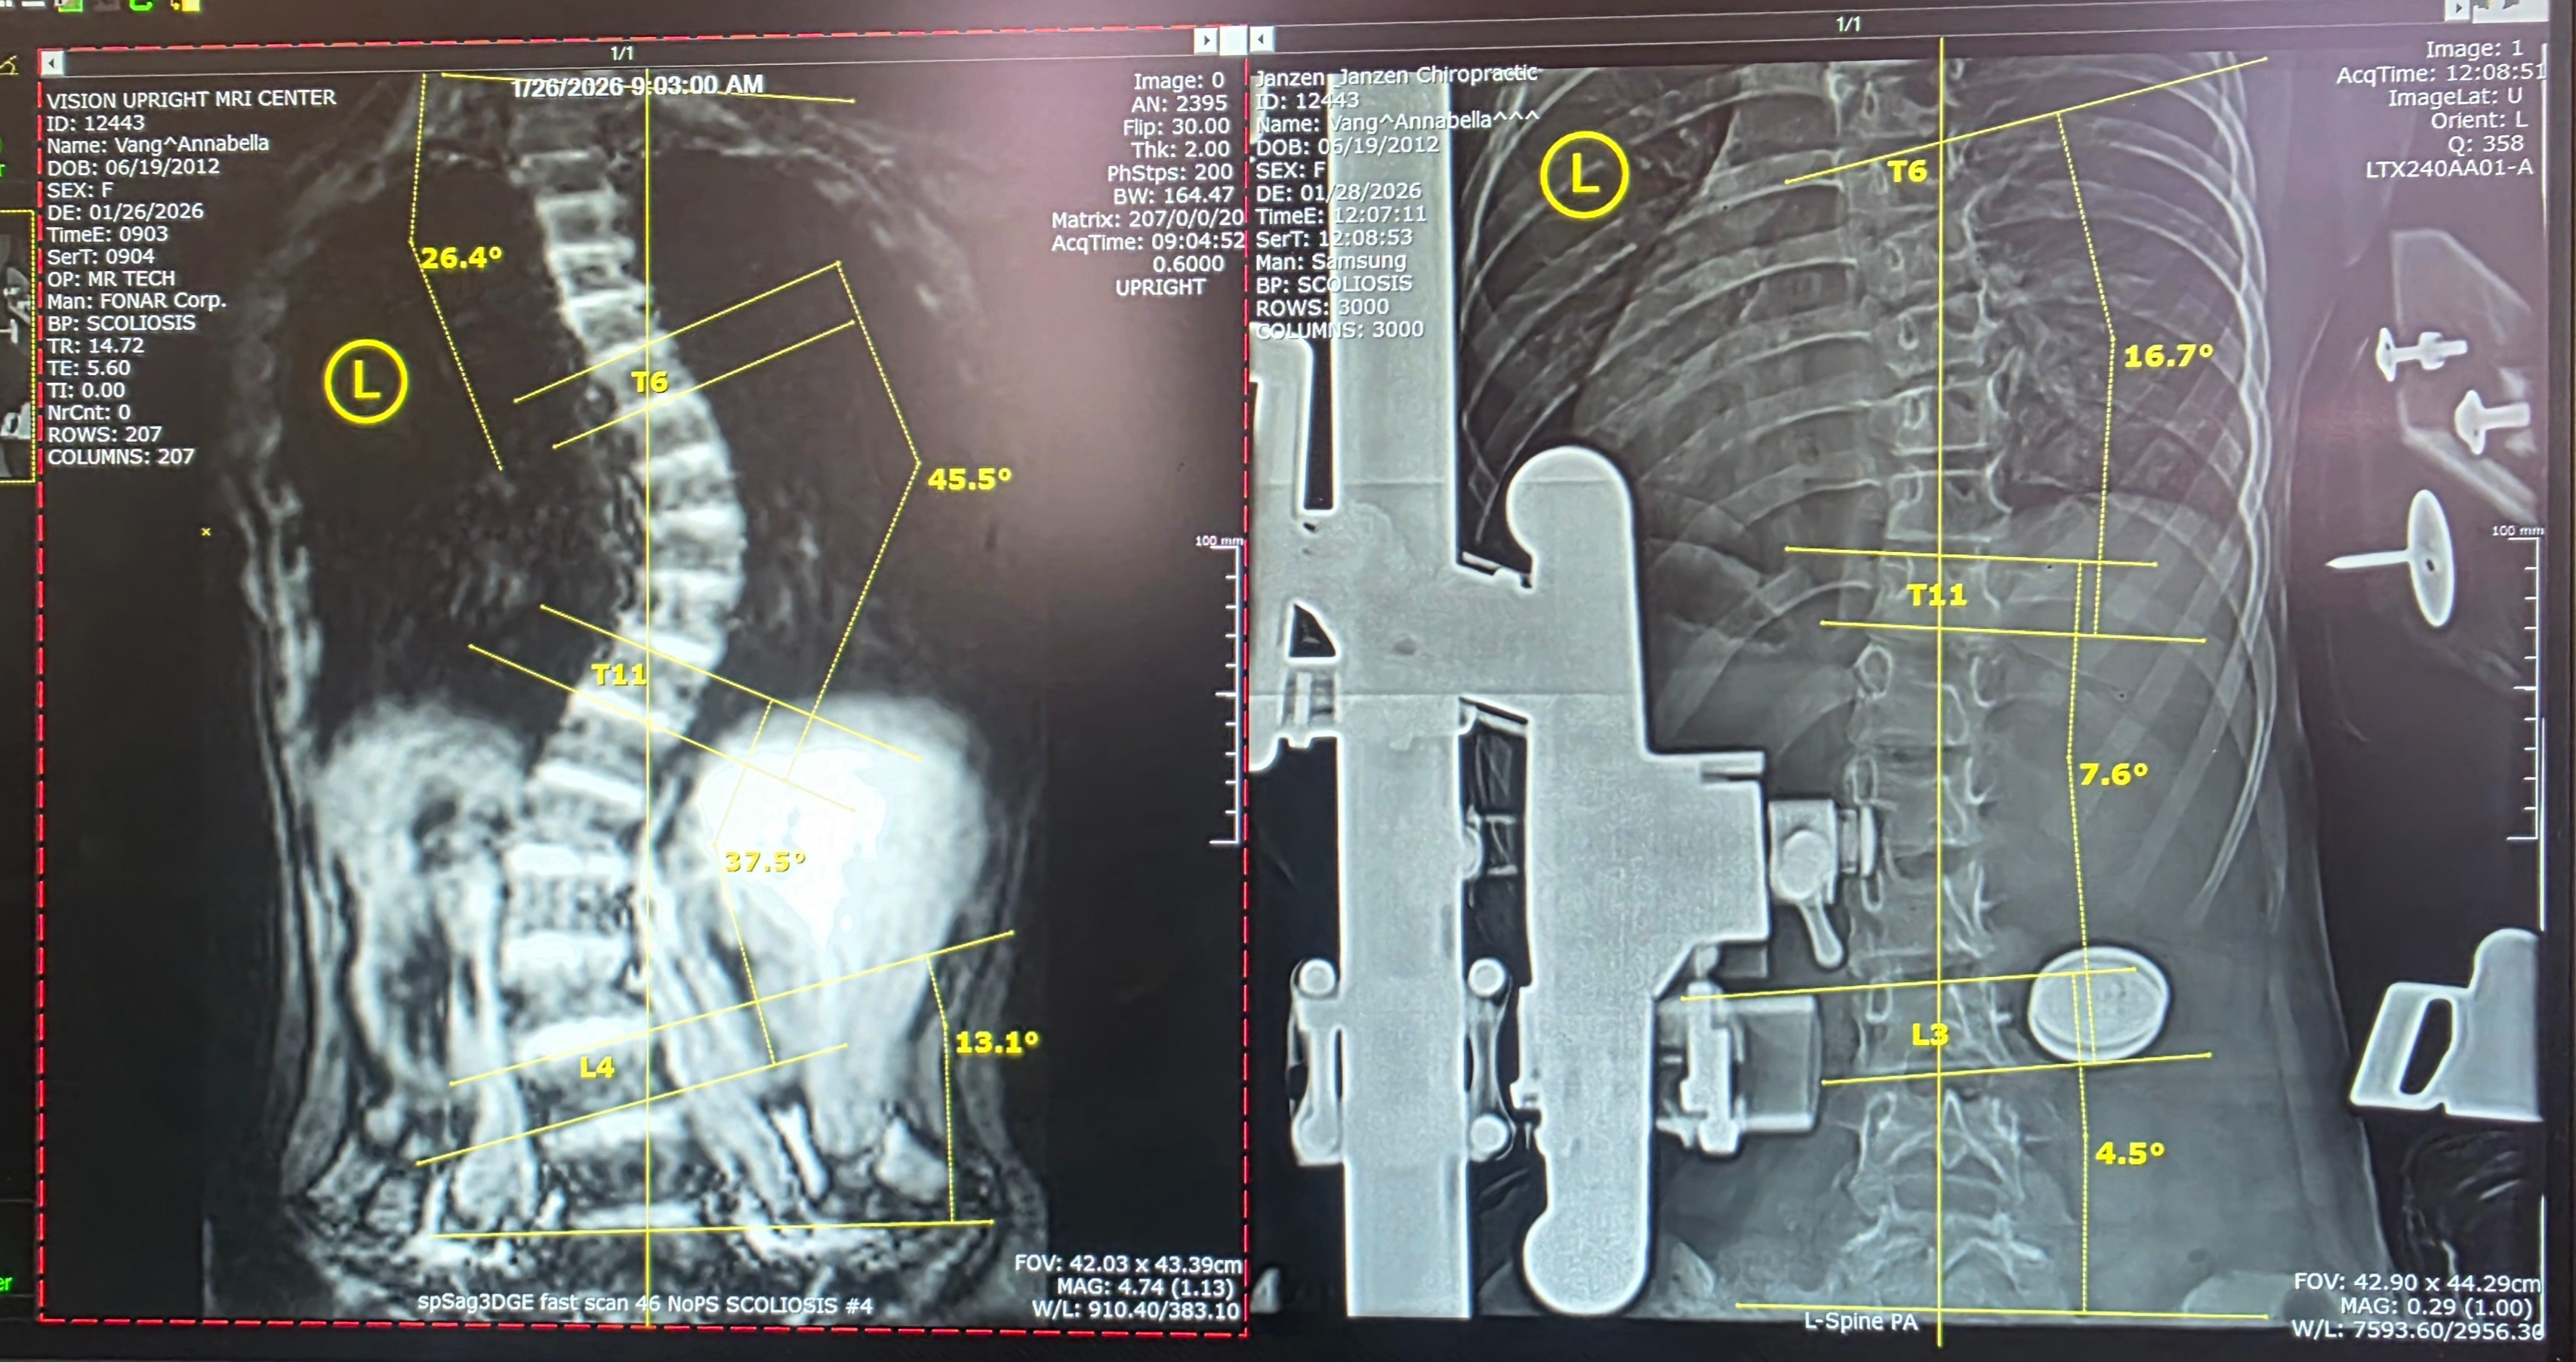

We did a lot of research and found a place called "Scoliosis Care Center By Janzen and Janzen" located in San Jose, California. Within the week, we made the three hour long trip over to San Jose where I got my first MRI. The MRI revealed how severe my scoliosis really is. Doctor M. Janzen at Scoliosis Care Center shared the devastating news that my scoliosis is an S-shape, with a severe curve above 43 degrees at the top, and a moderate curve at the bottom. We had a long conversation about treatment options I could receive there versus at a pediatric hospital. With the severity of my Cobb angle, most doctors would recommend we go with the irreversible route of scoliosis surgery. What's worse is that I am still growing (haven't hit my growth spurt yet) and because of that I might have to get future surgeries to correct any curves that can happen because I am getting taller.

Dr. Janzen gave me and my parents a lot of hope. He has shown us the treatment and results of other kids who have scoliosis. Many of them had severe scoliosis just like me, with angles well above 40 degrees, and they were able to reduce the curvature drastically.